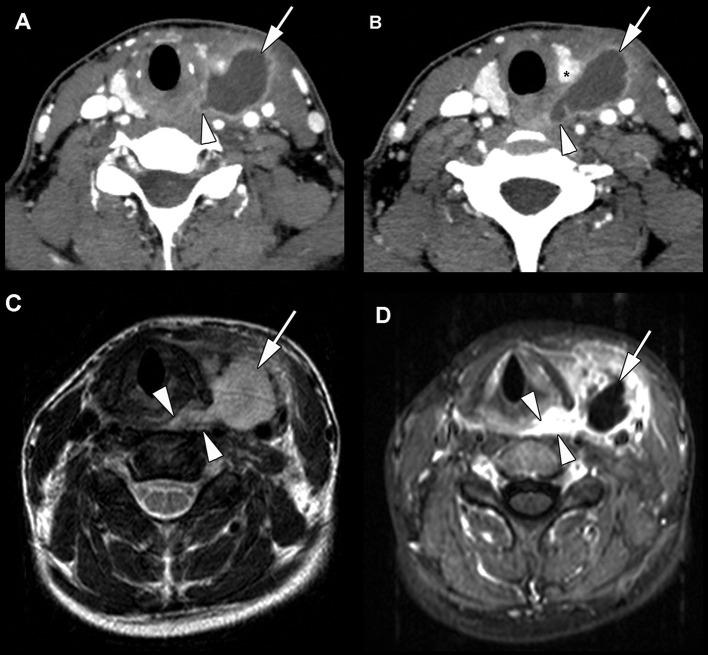

Fourth branchial anomalies, the rarest among anomalies of the branchial apparatus, often present diagnostic and therapeutic challenges. We evaluated the clinical presentation and radiographic features, the treatment and the long-term outcome of patients in this setting. Of 12 patients treated in the University Hospitals Leuven from 2004 until 2020, 12 variables were collected: date of birth, gender, age of onset of the symptoms, age at final diagnosis, presentation, laterality, previous procedures, diagnostic tools, treatment (open neck surgery, endoscopic laser excision, or combination), complications, recurrence, and period of follow-up. Descriptive statistics were calculated and results were compared to the existing literature. The most common clinical manifestations were recurrent neck infections with and without abcedation. Definitive diagnosis using direct laryngoscopy, visualizing the internal sinus opening, was possible in all patients. A CT study revealed the typical features of fourth branchial anomalies in seven patients out of nine, an ultrasound study in five out of nine patients. All patients underwent open neck surgery. If this was insufficient, secondary endoscopic laser resection of the ostium at the apex of the piriform sinus was performed ( = 4). In eight patients a thyroid lobectomy was needed for safe complete resection. Postoperative complications were minimal and at long-term, none of the patients showed further recurrence. Average time of follow-up was 8.6 years. Direct laryngoscopy and CT are the most accurate diagnostic tools. Our recommended treatment schedule consists of complete excision of the sinus tract by open neck surgery as the primary treatment because this ensures the best results. In case of recurrence afterwards, endoscopic laser resection of the pharyngeal ostium solved the problem.

第四鳃裂异常是鳃器异常中最为罕见的,常常带来诊断和治疗方面的挑战。我们评估了该情况下患者的临床表现、影像学特征、治疗方法及长期预后。在2004年至2020年于鲁汶大学医院接受治疗的12例患者中,收集了12项变量:出生日期、性别、症状出现年龄、最终诊断年龄、临床表现、病变侧别、既往治疗、诊断工具、治疗方法(颈部开放手术、内镜激光切除或联合治疗)、并发症、复发情况及随访时间。计算描述性统计数据,并将结果与现有文献进行比较。最常见的临床表现是伴有或不伴有脓肿形成的复发性颈部感染。所有患者均可行直接喉镜检查明确诊断,观察内部窦口。9例患者中的7例通过CT检查显示出第四鳃裂异常的典型特征,9例患者中的5例通过超声检查显示。所有患者均接受了颈部开放手术。若手术不充分,则对梨状窝尖部的窦口进行二期内镜激光切除(n = 4)。为安全完整切除,8例患者需要行甲状腺叶切除术。术后并发症极少,长期来看,所有患者均未出现进一步复发。平均随访时间为8.6年。直接喉镜检查和CT是最准确的诊断工具。我们推荐的治疗方案是以颈部开放手术完整切除窦道作为主要治疗方法,因为这样能确保最佳效果。若之后出现复发,内镜激光切除咽侧窦口可解决问题。